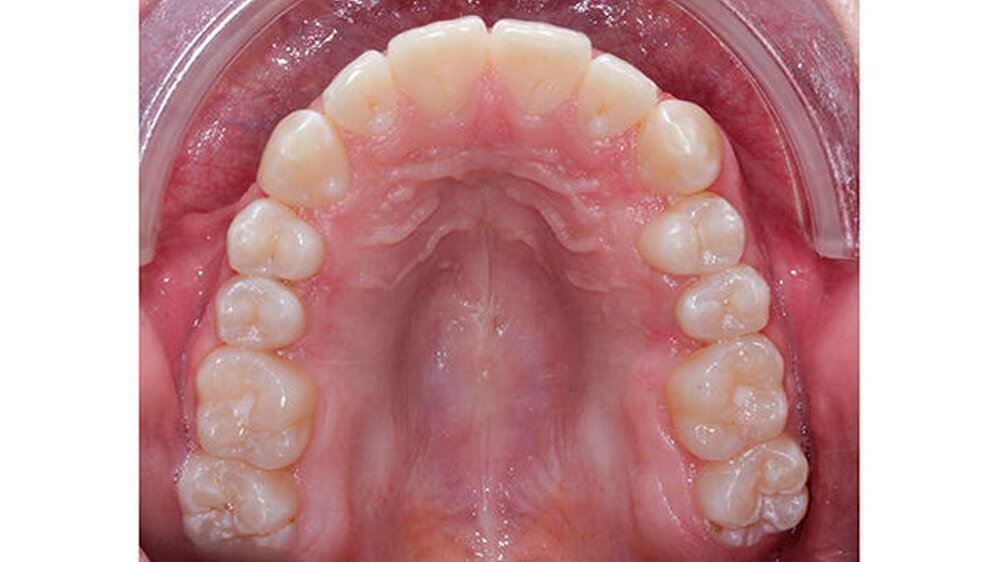

Nach dreijähriger kieferorthopädischer Behandlung konnte die Patientin entbändert werden. Eine Stabilisierungsphase mit herausnehmbaren Essixschienen folgte. Nach Ende der aktiven Behandlungszeit waren die Therapieziele weitgehend erfolgreich umgesetzt worden.